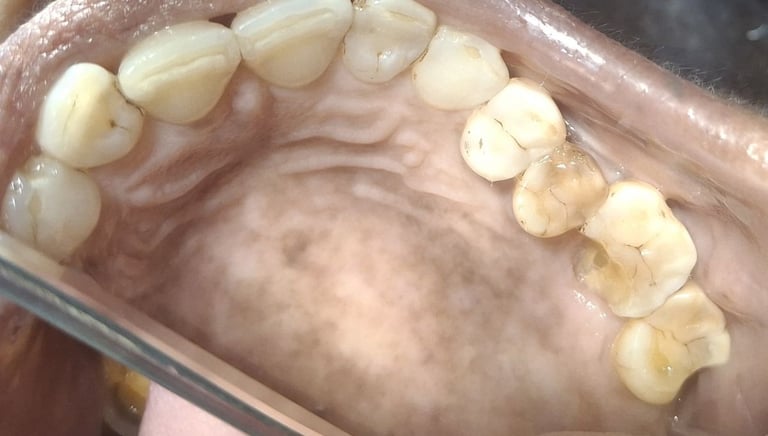

Clinical pictures of teeth requiring RCT

All images are of real cases of teeth where Root canal treatment was performed to remove infection and preserve the natural tooth restoring normal chewing and function of teeth.